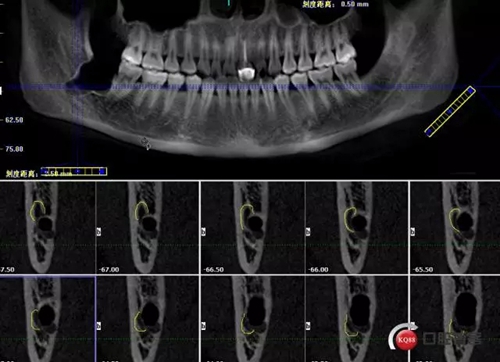

1498615727_411668.png

牙齒下1/3神經(jīng)管在頰側(cè)